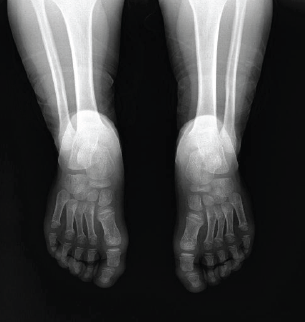

Bilateral Kohler’s Disease in a 5-Year-Old Girl: A Case Report

Furkan Soy , Ibrahim Deniz Canbeyli , Meric Cirpar , Yasin Kozan , Sancar Serbest

………………………………p.148-150